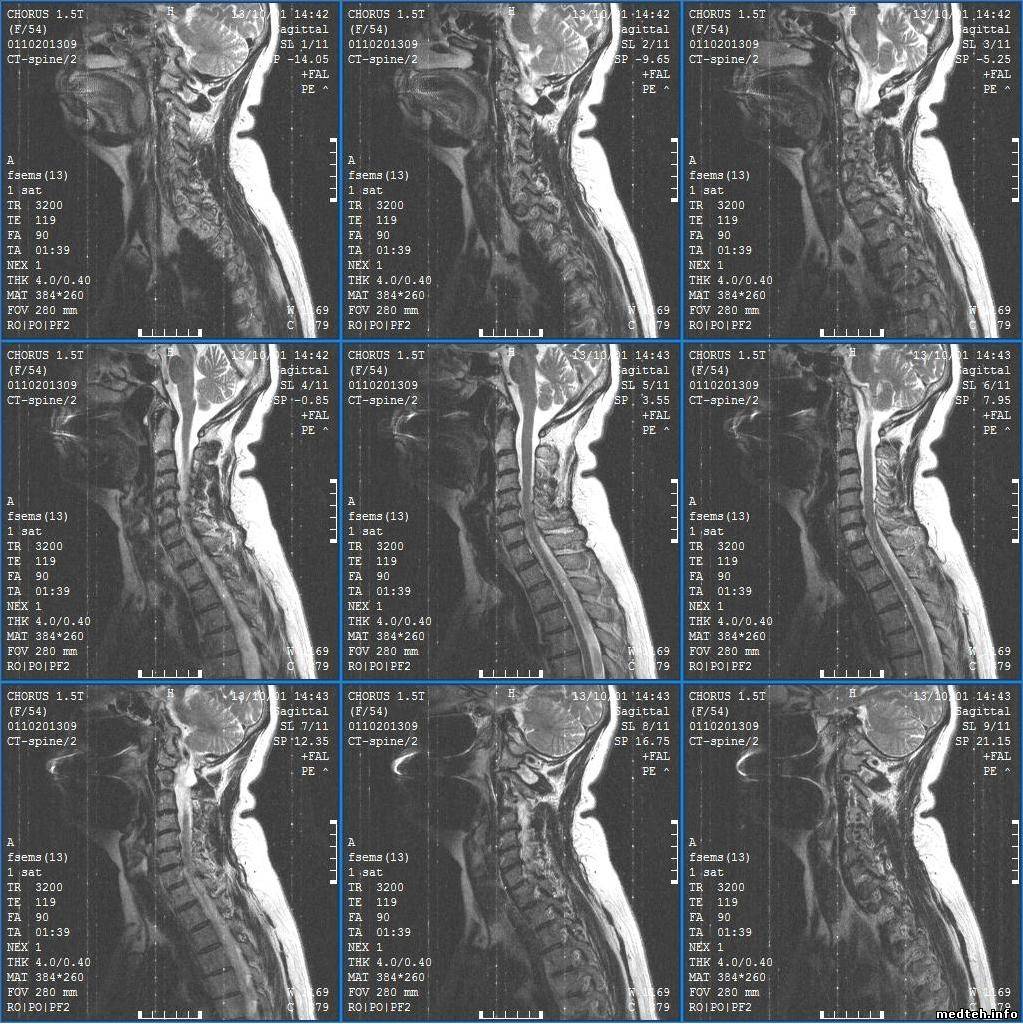

Здравствуйте, на полуторатесловом мрт аппарате замечено ухудшение изображения, особенно на шейной катущке, также постоянные линии (на всех катушках). Какие причины могли привести к такому? Вызывали сервисников, они повыкручивали лампочки, сняли камеру в комнате исследования (сказали что метал влияет на сигнал), погоняли фантом и уехали, ждем ответа.

6338681.jpg (241.4 Kb)

РЧ-помехи, судя по картинке. Если направление линий совпадает с направлением фазового кодирования - 90% что это оно.